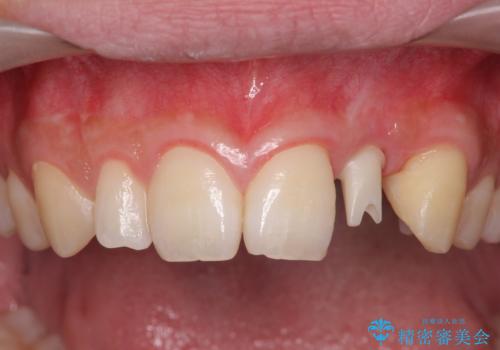

- 前歯の永久歯が元々なく、乳歯を失ったタイミングで前歯の審美性の回復を求めて来院されました。

機能・審美性の回復手段として、インプラント治療・ブリッジ・部分床義歯が考えられます。

それぞれの治療に特徴がありますが、取り外しの必要がなく隣の歯を削る必要も必要ないインプラント治療を選択されました。

前歯部にインプラントを埋入し、きれいに仕上げるためには骨の造成技術や歯肉の厚みを増すような処置を行い、インプラント周囲の環境を整備することが肝要です。